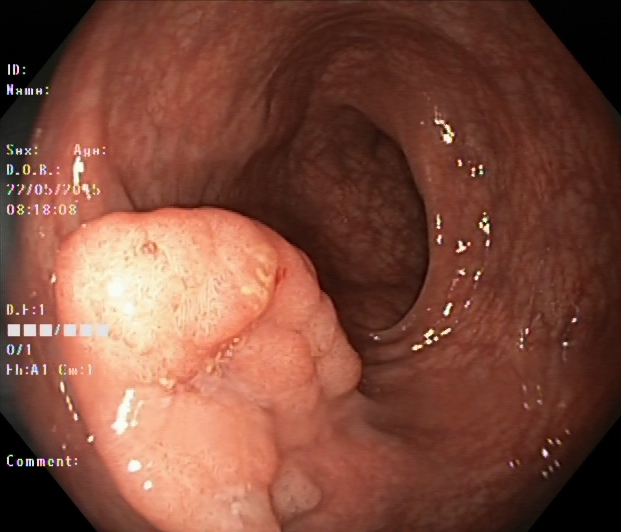

An automatic and efficient Computer-Aided Diagnosis (CAD) system in a clinic could assist medical experts during the endoscopic and colonoscopy procedure to improve the detection rate by finding unrecognized lesions and act as a second observer by providing better insights to the gastroenterologist concerning the presence and types of lesions. With this inspiration, we conducted five experiments to classify 161616 classes of GI tract conditions for the Medico Multimedia Task at MediaEval 2018 (Pogorelov et al., 2018b). One example for each of the 16 classes is depicted in Figure 1.

Figure 1. Sample images of GI findings. Each image represents one of the 16 classes from the dataset used for the Medico 2018 challenge (Pogorelov et al., 2017c, a).